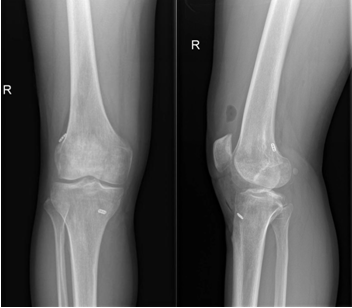

近日,一名31岁男性因打篮球扭伤致“右膝关节疼痛伴行走不稳半年”入院,术前诊断:前交叉韧带部分断裂。考虑患者年轻且有较高的运动恢复需求,在骨科病院刘时璋主任医师的指导下,由冯敏副主任医师主刀完成六合彩网站

首例关节镜辅助下前交叉韧带损伤“保残+全内”重建术。患者第二日即下地活动,第三天顺利出院。